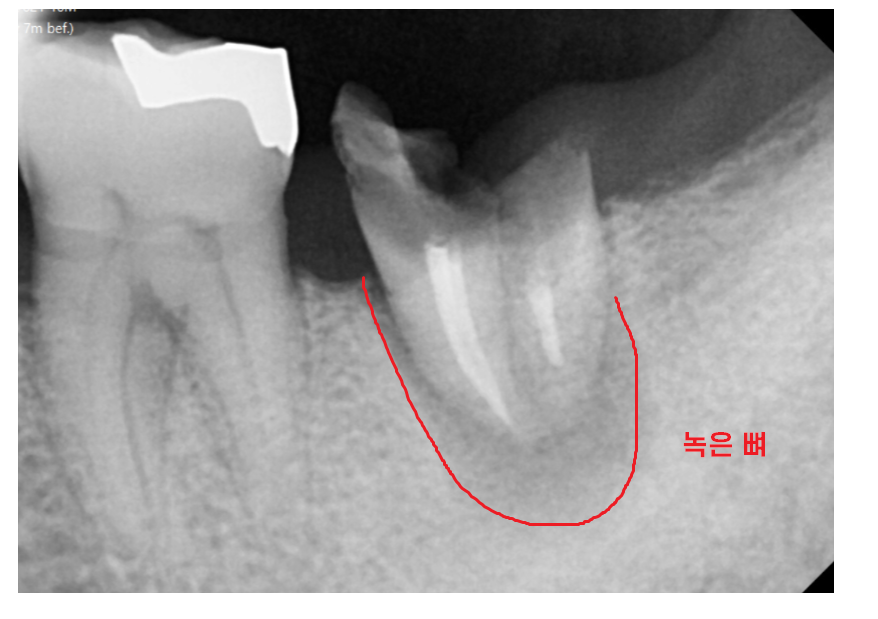

외관상의 문제보다

뿌러지고 방치 되면서

치아 주변 뼈가 녹은게 관찰됩니다.

통증이 있는 상태라

해결을 위해서는 치아를 뽑아야 했는데요.